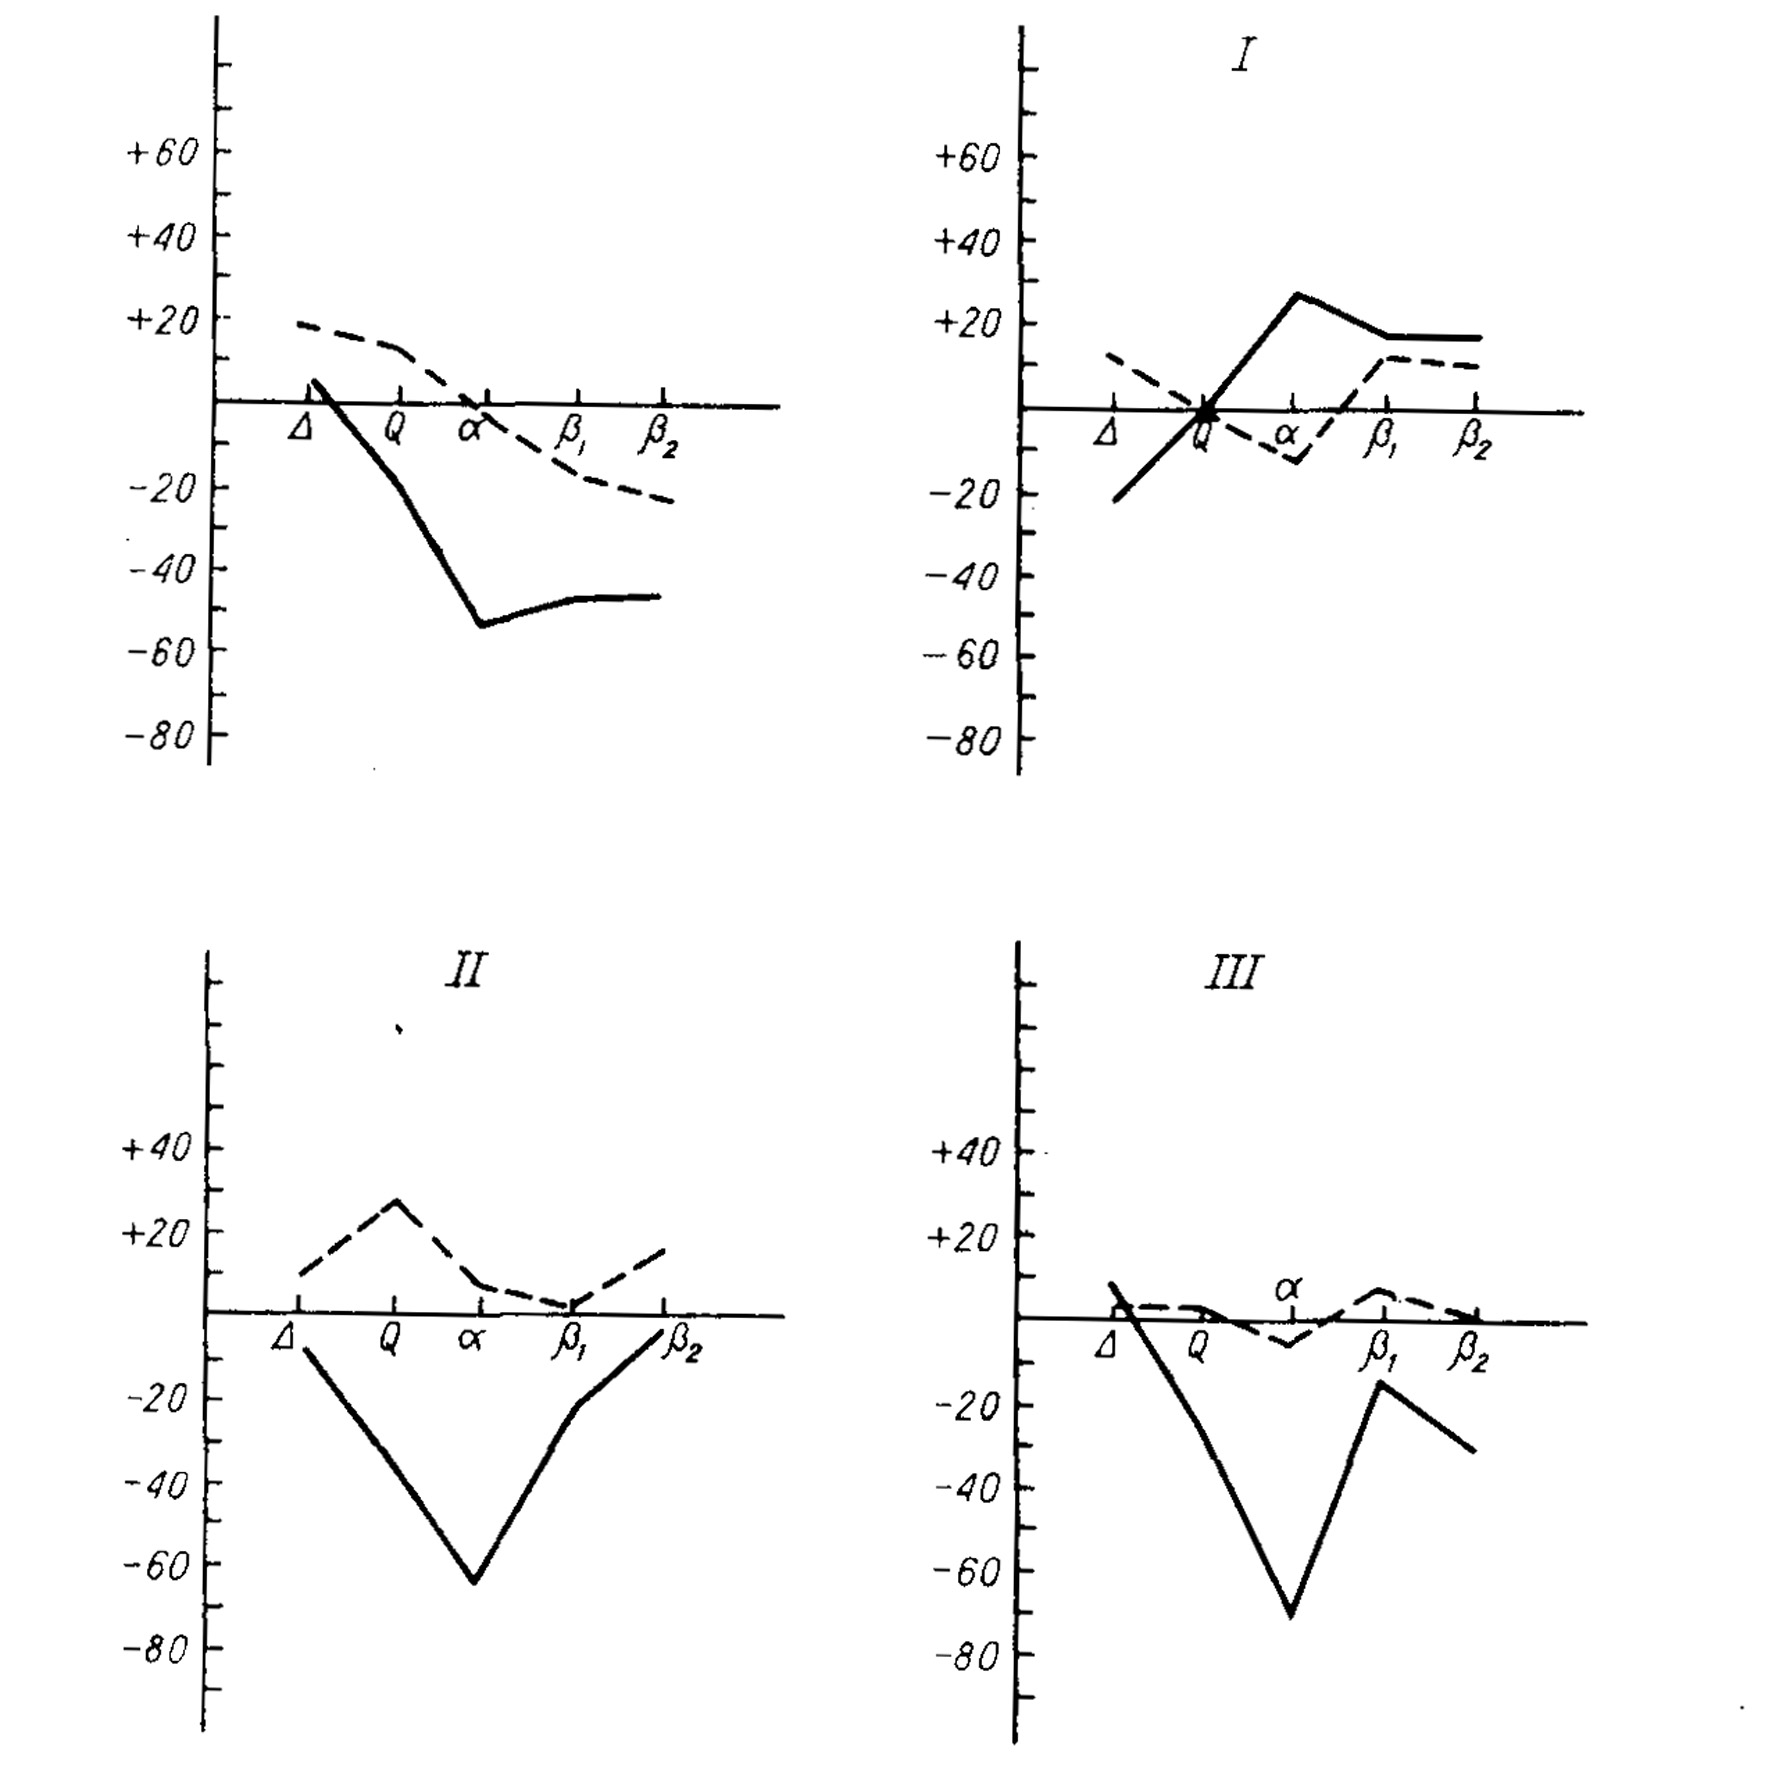

Lurija ha assegnato una particolare importanza alla terza unità funzionale. grazie ad essa che il comportamento umano si distinguerebbe dal comportamento degli animali. « L'uomo non solo non reagisce passivamente all'informazione in arrivo, ma crea intenzioni, forma piani e programmi delle sue azioni, controlla la loro esecuzione e regola il suo comportamento in modo che si conformi alla sua attività cosciente, confrontando gli effetti delle sue azioni con le intenzioni originali e correggendo ogni errore che abbia fatto. » L'importanza dei lobi frontali nel comportamento umano risulta indirettamente dallo studio della loro evoluzione filogenetica e dall'osservazione che essi divengono una formazione tipica del cervello dell'uomo. Si deve però proprio alle ricerche cliniche e sperimentali di Lurija e dei suoi allievi la dimostrazione che i lobi frontali hanno una funzione basilare. Le lesioni di queste regioni cerebrali producono una vasta varietà di sintomi (sindrome frontale) che risultano in gravi alterazioni del comportamento e dell'attività mentale nel loro complesso. In primo luogo, lesioni ai lobi frontali danneggiano la regolazione dei livelli di attivazione, disturbando le prestazioni comportamentali che richiedono uno stato di vigilanza ottimale. Il deficit comportamentale si correla ad alterazioni dei pattern elettrofisiologici normali (riflesso psicogalvanico, elettroencefalogramma, ecc.) (fig. 24).

Fig. 24. Reazioni elettroencefalografiche a stimoli rilevanti (linea continua) e irrilevanti (linea tratteggiata) in soggetti normali (in alto a sinistra) e in soggetti con lesioni cerebrali (I: lesioni delle regioni medio-basali dei lobi -frontali; II: lesioni in altre regioni dei lobi frontali; III: lesioni nelle parti posteriori del cervello). Si noti che la depressione in percentuale del ritmo alfa allo stimolo rilevante è sempre presente in tutti i gruppi di soggetti e maggiore che negli altri ritmi (delta, theta, beta), eccetto che nei soggetti con lesioni frontali medio-basali (da E. D. Flomskaya (Chomskaa), Acta neurobsolograe experirnentalis, 1973, v. 33, pp. 509-522).